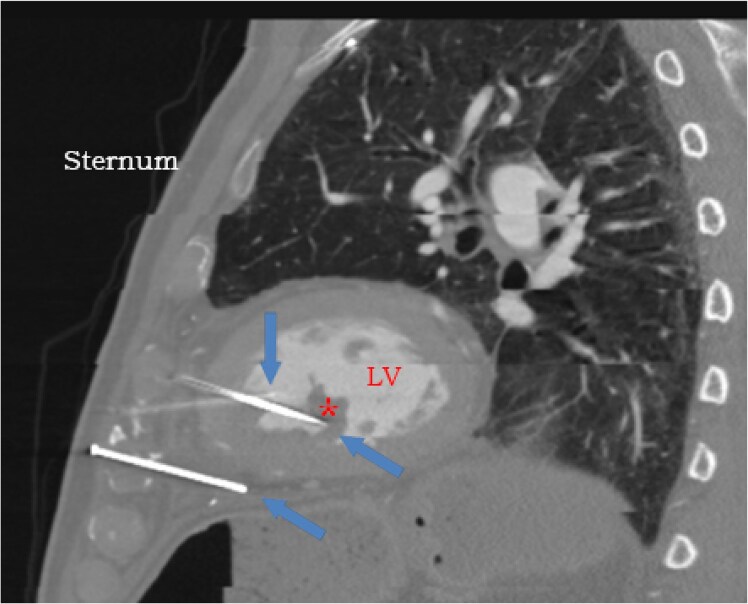

Case summary: A frail 83-year-old male who had undergone coronary artery bypass grafting surgery 20 years ago presented with encephalopathy. He had persistent bacteraemia. Chest computed tomography revealed three metal nails penetrating the anterior thoracic wall through the myocardium. Later, we learned that he had attempted suicide 2 years ago by shooting himself in the chest using a nail gun. Conservative non-surgical approach was pursued at that time given his multiple comorbidities. We adopted a conservative approach again. He survived for additional 6 months on chronic suppressive antimicrobial therapy but ultimately passed away from pneumonia.